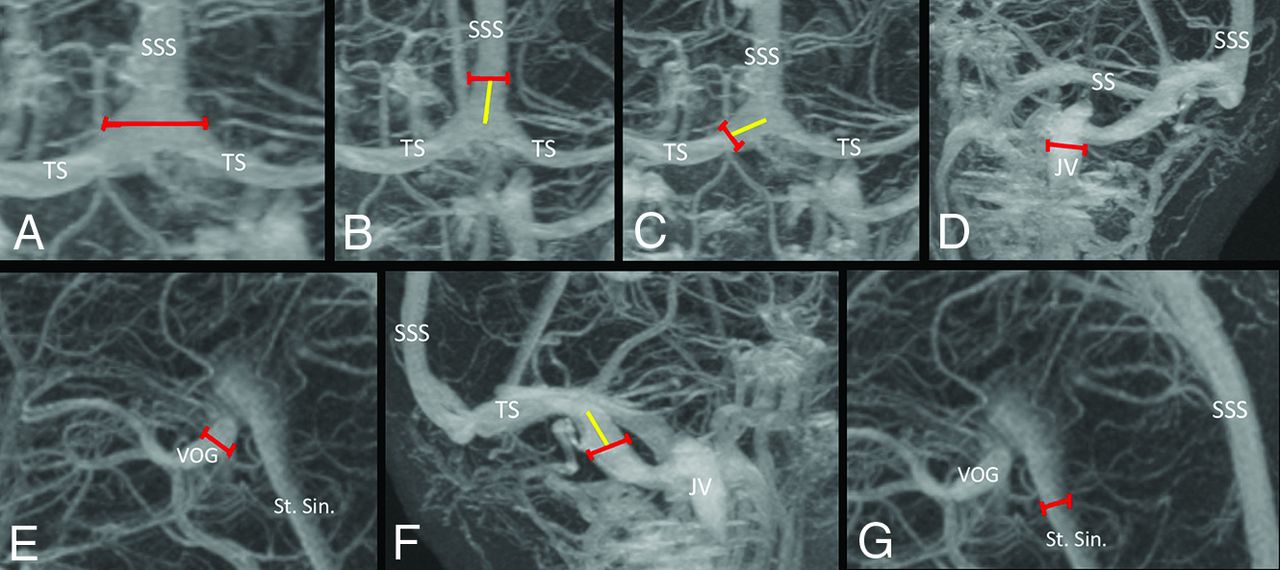

The anatomy of the transverse sinus system was classified as codominant, right-side-dominant, left-side-dominant, right-side-atretic, or left-side-atretic. All measurements were performed in QREADS imaging software (Mayo Clinic). Figure 1 is an example of the measurement process, and Fig 2 shows sample patterns of transverse sinus anatomy.

Measurement strategy for determining the diameter of components of dural venous sinuses. A, The maximal diameter of torcula is obtained. Superior sagittal sinus (B) and bilateral transverse sinuses (C) are measured (red line) 1 cm away from the center of the torcula (yellow line). D, The maximal diameter of the internal jugular vein is measured at the skull base. E, The maximal diameter of the vein of Galen is obtained. F, The sigmoid sinuses are measured (red line) 1 cm distal to the transverse sigmoid junction (yellow line). G, The maximal diameter of the straight sinus is obtained. JV indicates jugular vein; SS, sigmoid sinus; St. Sin., straight sinus; TS, transverse sinus; SSS, superior sagittal sinus; VOG, vein of Galen.